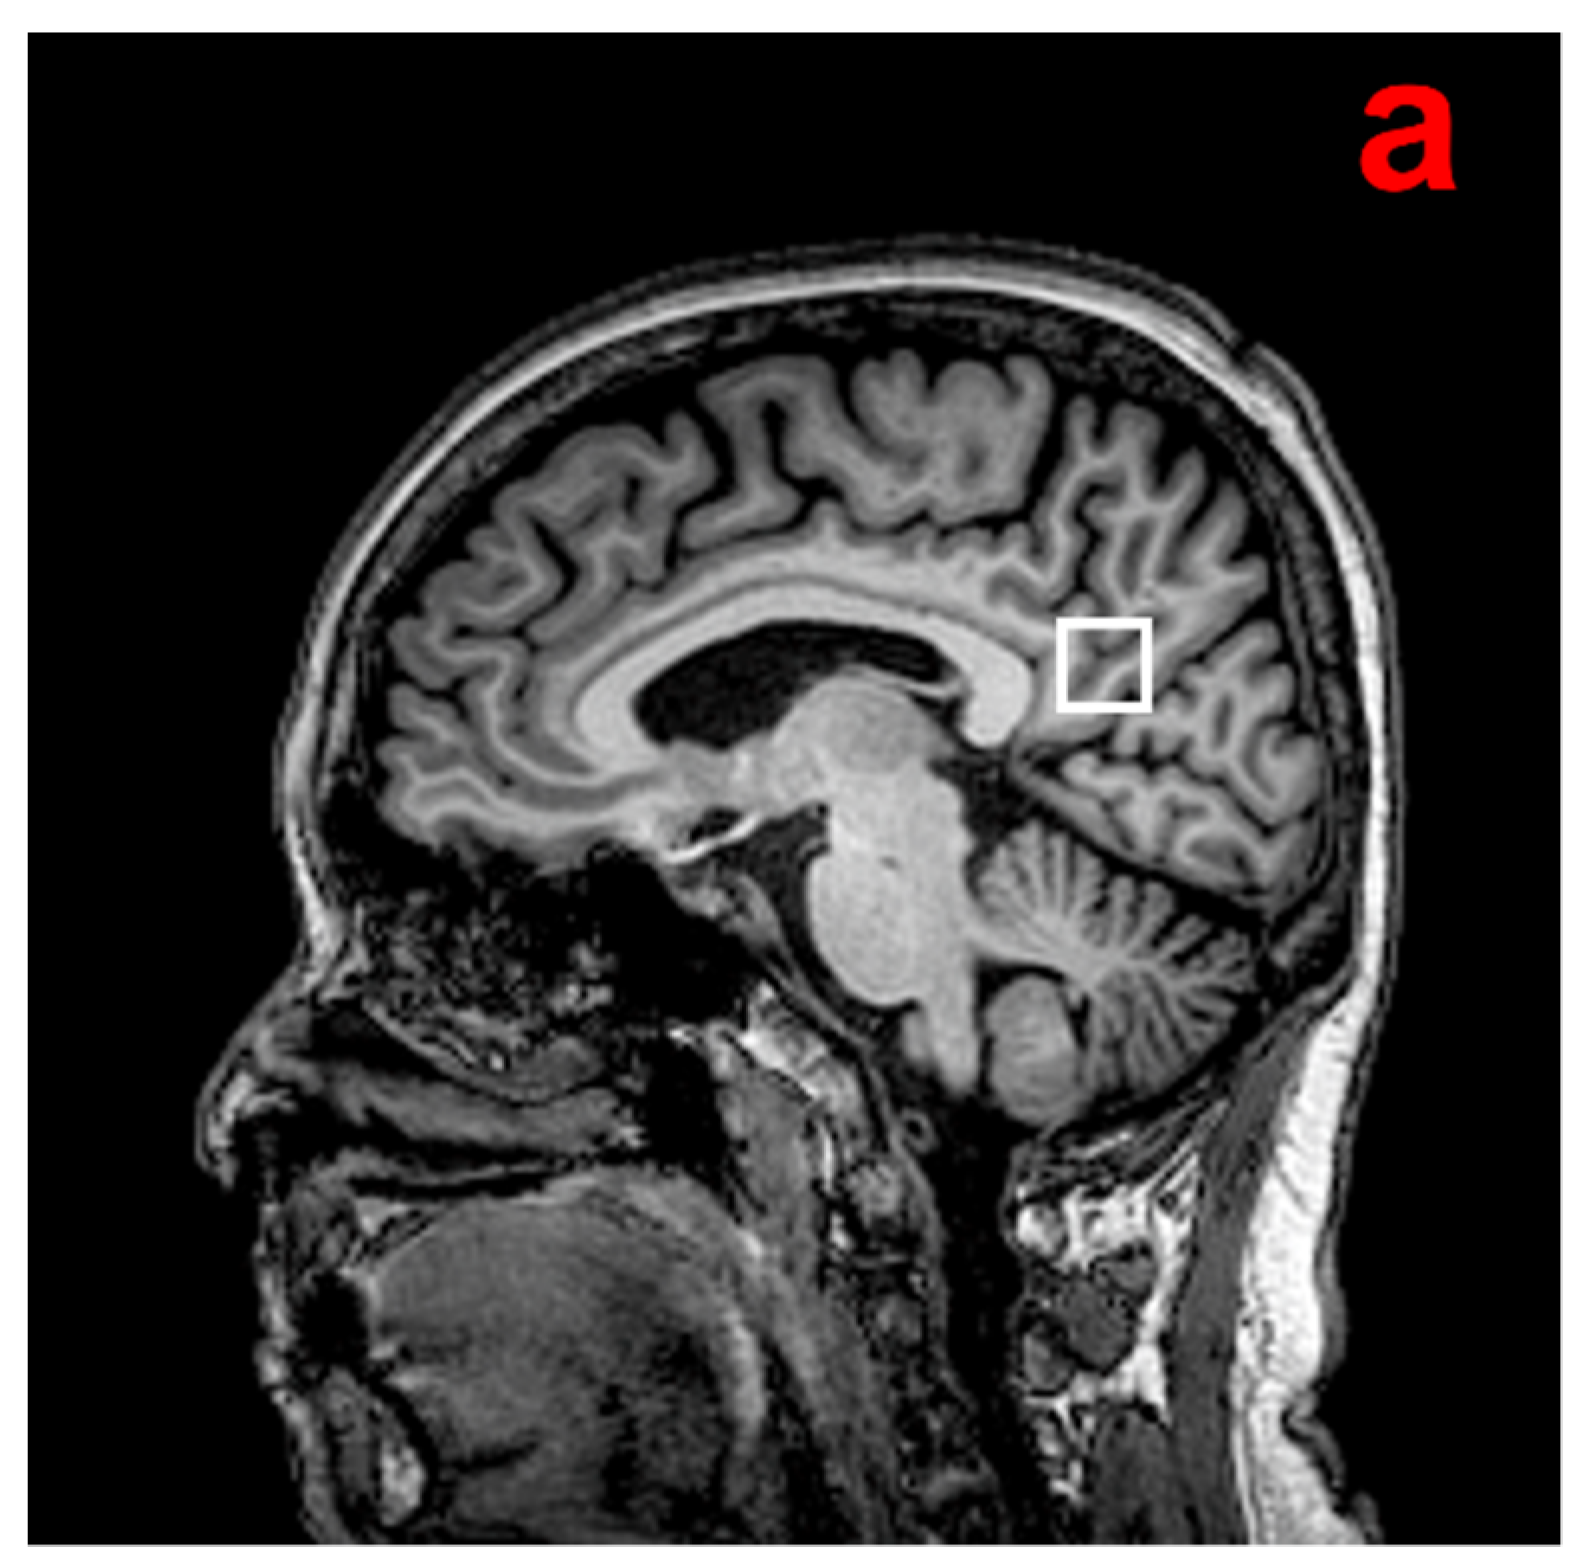

1H-MRS examination was performed using the point-resolved spectroscopy (PRESS) sequence (TR = 2000 ms, TE = 32 ms, bandwidth = 2000 Hz, 1024 data points, 128 excitations, acquisition time = 4 min 52 s). An 8 cm3 (2 × 2 × 2 cm) voxel that mainly included the posterior cingulate cortex (PCC)/precuneus region was manually placed on a midsagittal T1-weighted image, including the right and left PCC (Figure 1). This region demonstrates early metabolic reduction over the course of AD [16]. It is also a well-defined midline structure from which spectra can be acquired with high reproducibility and high quality [7].

Figure 1.

(a) Example of the 1H-MRS voxel localization. (b) MR proton spectra. mI, myoInositol; Cho, choline-containing compound; Cr, creatine; GSH, glutathione; Glx, glutamate and glutamine; NAA, N-acetylaspartate; ppm, parts per million [17].